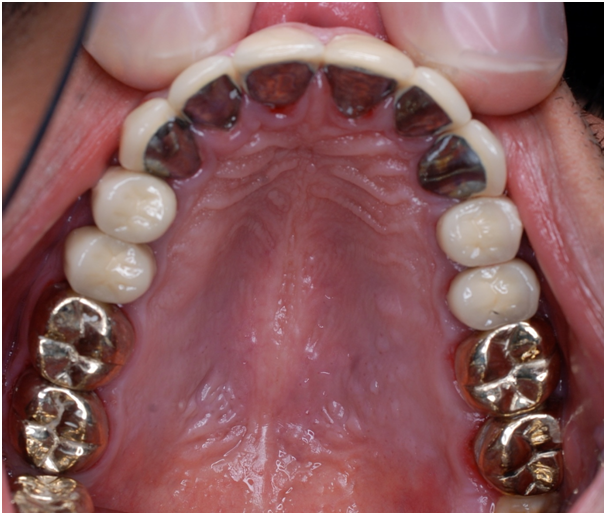

Figure 17 Final upper arch view.

Esthetic, phonetics and occlusion were checked after cementation the temporary crowns with temporary (Pro. Temp) luting agent. To avoid any functional problems, the patient was instructed to give the temporaries a period of trial for 2 weeks. Intra occlusal relationship was repeated at this stage again. When the patient reported no discomfort, the final crowns were constructed. Final crowns were cemented using resin composite (Rely X Unicem) luting agent. Teeth restored were # 2, 3, 4, 5, 6, 7, 8, 9,10, 11, 12, 13, 14, 15,18, 19, 20, 21, 22, 23, 24, 25, 26, 27, 28, 29, 30 and 31. Postoperative pictures, x-rays, and impressions were taken (Figure 9−19). The case had a good prognosis considering the patient, good general health and proper attitude toward his oral hinging reported during the maintenance and treatment phases. The periodontium is in functional health status, using gold alloys to restore posterior teeth as well as porcelain-fused to metal crowns to restore anterior teeth conserve tooth structures by minimizing the amount of tooth structure to be cut.